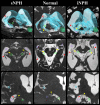

To clarify the pathogenesis of two different types of adult-onset normal-pressure hydrocephalus (NPH), we investigated cerebrospinal fluid distribution on the high-field three-dimensional MRI. The subarachnoid spaces in secondary NPH were smaller than those in the controls, whereas those in idiopathic NPH were of similar size to the controls. In idiopathic NPH, however, the basal cistern and Sylvian fissure were enlarged in concurrence with ventricular enlargement towards the z-direction, but the convexity subarachnoid space was severely diminished. In this article, we provide evidence that the key cause of the disproportionate cerebrospinal fluid distribution in idiopathic NPH is the compensatory direct CSF communication between the inferior horn of the lateral ventricles and the ambient cistern at the choroidal fissure. In contrast, all parts of the subarachnoid spaces were equally and severely decreased in secondary NPH. Blockage of CSF drainage from the subarachnoid spaces could cause the omnidirectional ventricular enlargement in secondary NPH.